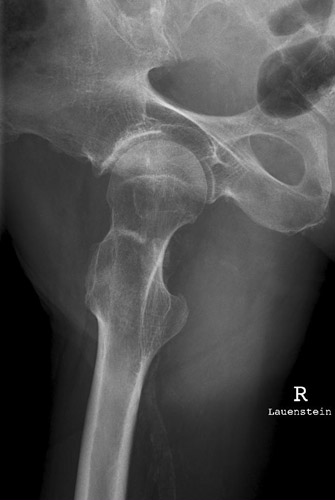

Die obere Begrenzung des Trochanter majors reicht fasst bis zum Hüftkopf. Er überdeckt zum Teil den Schenkelhals und dessen distalen Teil. Der Trochanter minor bildet sich weit unterhalb des Trochanter major im Schaft des Oberschenkels, randbildend, ab. Der femur wurde zu weit abgespreizt. oder fast seitliche Lagerung der Oberschenkels. Nicht die Oberschenkelachse soll zur Filmachse parallel stehen, sondern die Achse des Schenkelhalses.

Der Patient darf den Femur nur wenig nach außen abspreizen, damit stellt sich der Schenkelhals horizontal ein.